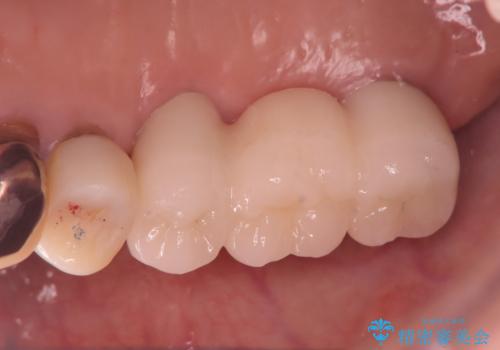

上下のインプラント治療する事によりしっかり奥歯で咬めるようになり、患者様は大変喜ばれていました。